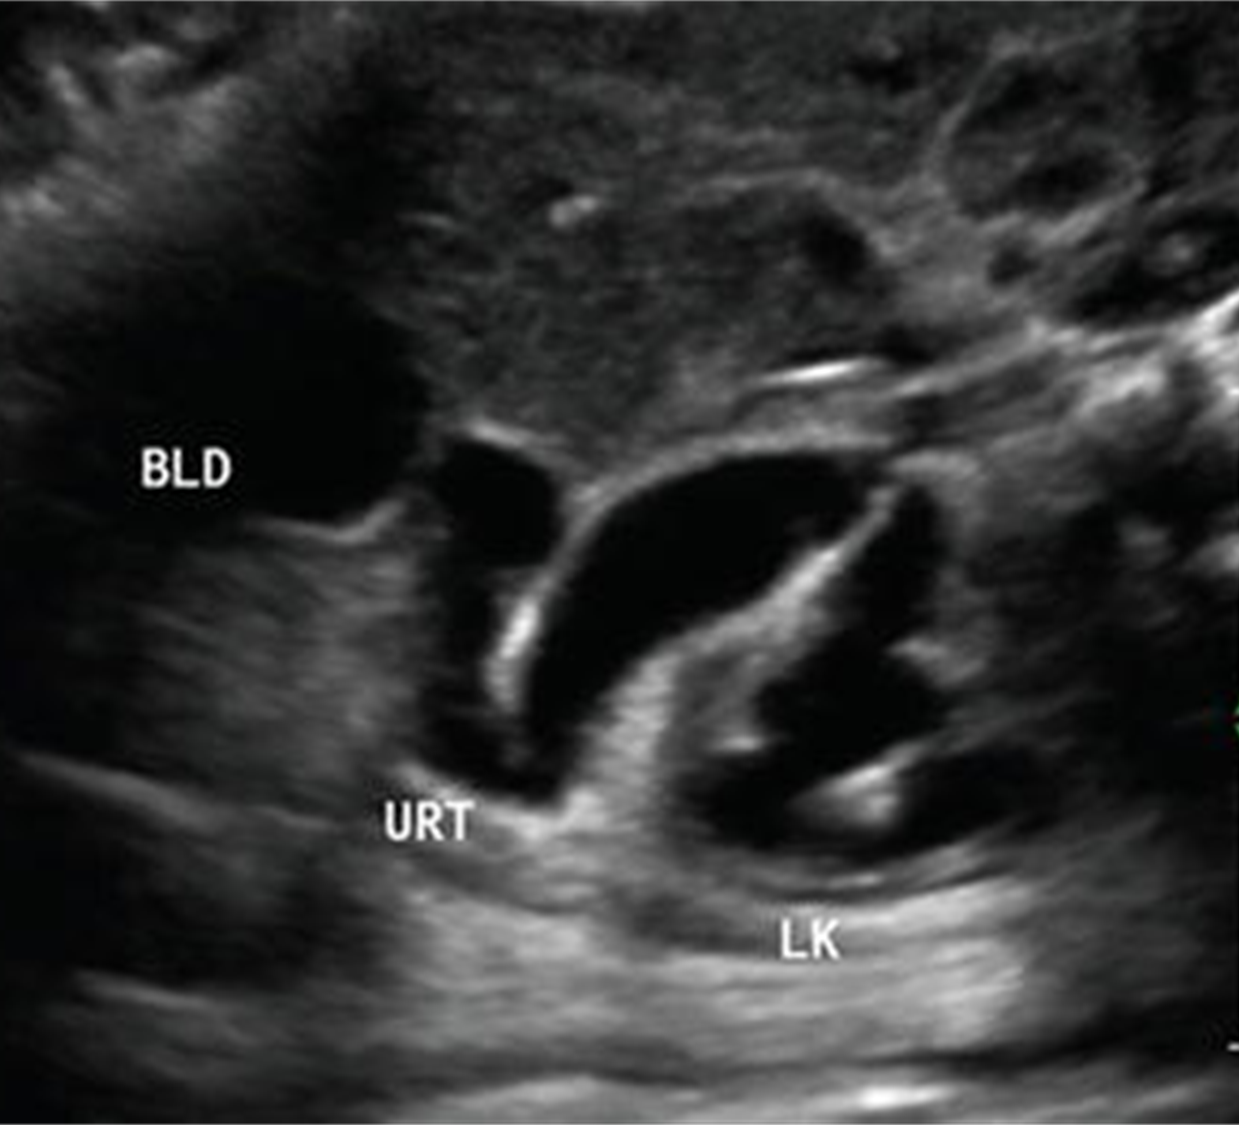

Uterocele